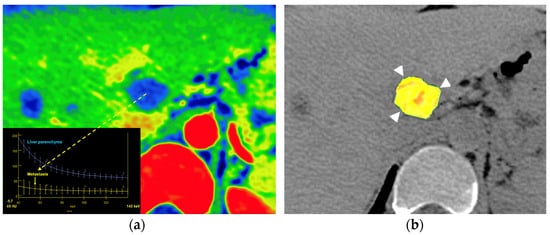

Another field of growing interest for the use of DECT is liver imaging. Advanced applications of liver DECT imaging include the assessment of fat and iron deposits and the calculation of the extracellular volume (ECV) (which is related to the degree of liver fibrosis). Although a non-contrast scan is preferred, recent studies have shown that DECT can accurately quantify liver fat even on contrast-enhanced images. In the case of liver iron content, both the attenuation difference of the liver between the low- and high-energy CT images or using an iron- or fat-specific material decomposition algorithm correlate well with the MR-based assessment of iron or fat accumulation [27,28,29,30] (Figure 9). The major limitations of the routine use of DECT in diffuse liver diseases are radiation and the additional software required for postprocessing. Finally, although DECT cannot directly detect or quantify fibrosis in the liver, the degree of hepatic fibrosis is strongly correlated with the ECV. The quantification of the ECV at a contrast-enhanced delayed phase (4–5 min) can be used to estimate the degree of hepatic fibrosis. A normalized iodine concentration of the liver (representing the ratio of the iodine concentration of the liver compared to that of the aorta) may reflect the amount of fibrosis based on the extent of iodine uptake [31].

Figure 23.

Metastatic colon cancer in the liver treated with chemotherapy. A color-coded iodine concentration map with a superimposed spectral curve (a) of the metastatic deposit (yellow arrow) compared to normal parenchyma shows no enhancement in the metastasis, suggesting extensive necrosis. A color-coded parametric map of entropy derived from texture analysis of iodine [no water] map superimposed on VUE image (b) evidence low entropy values in the metastatic deposit (postprocessing program Olea Sphere, version 3.0; Olea Medical, La Ciotat, Francia).